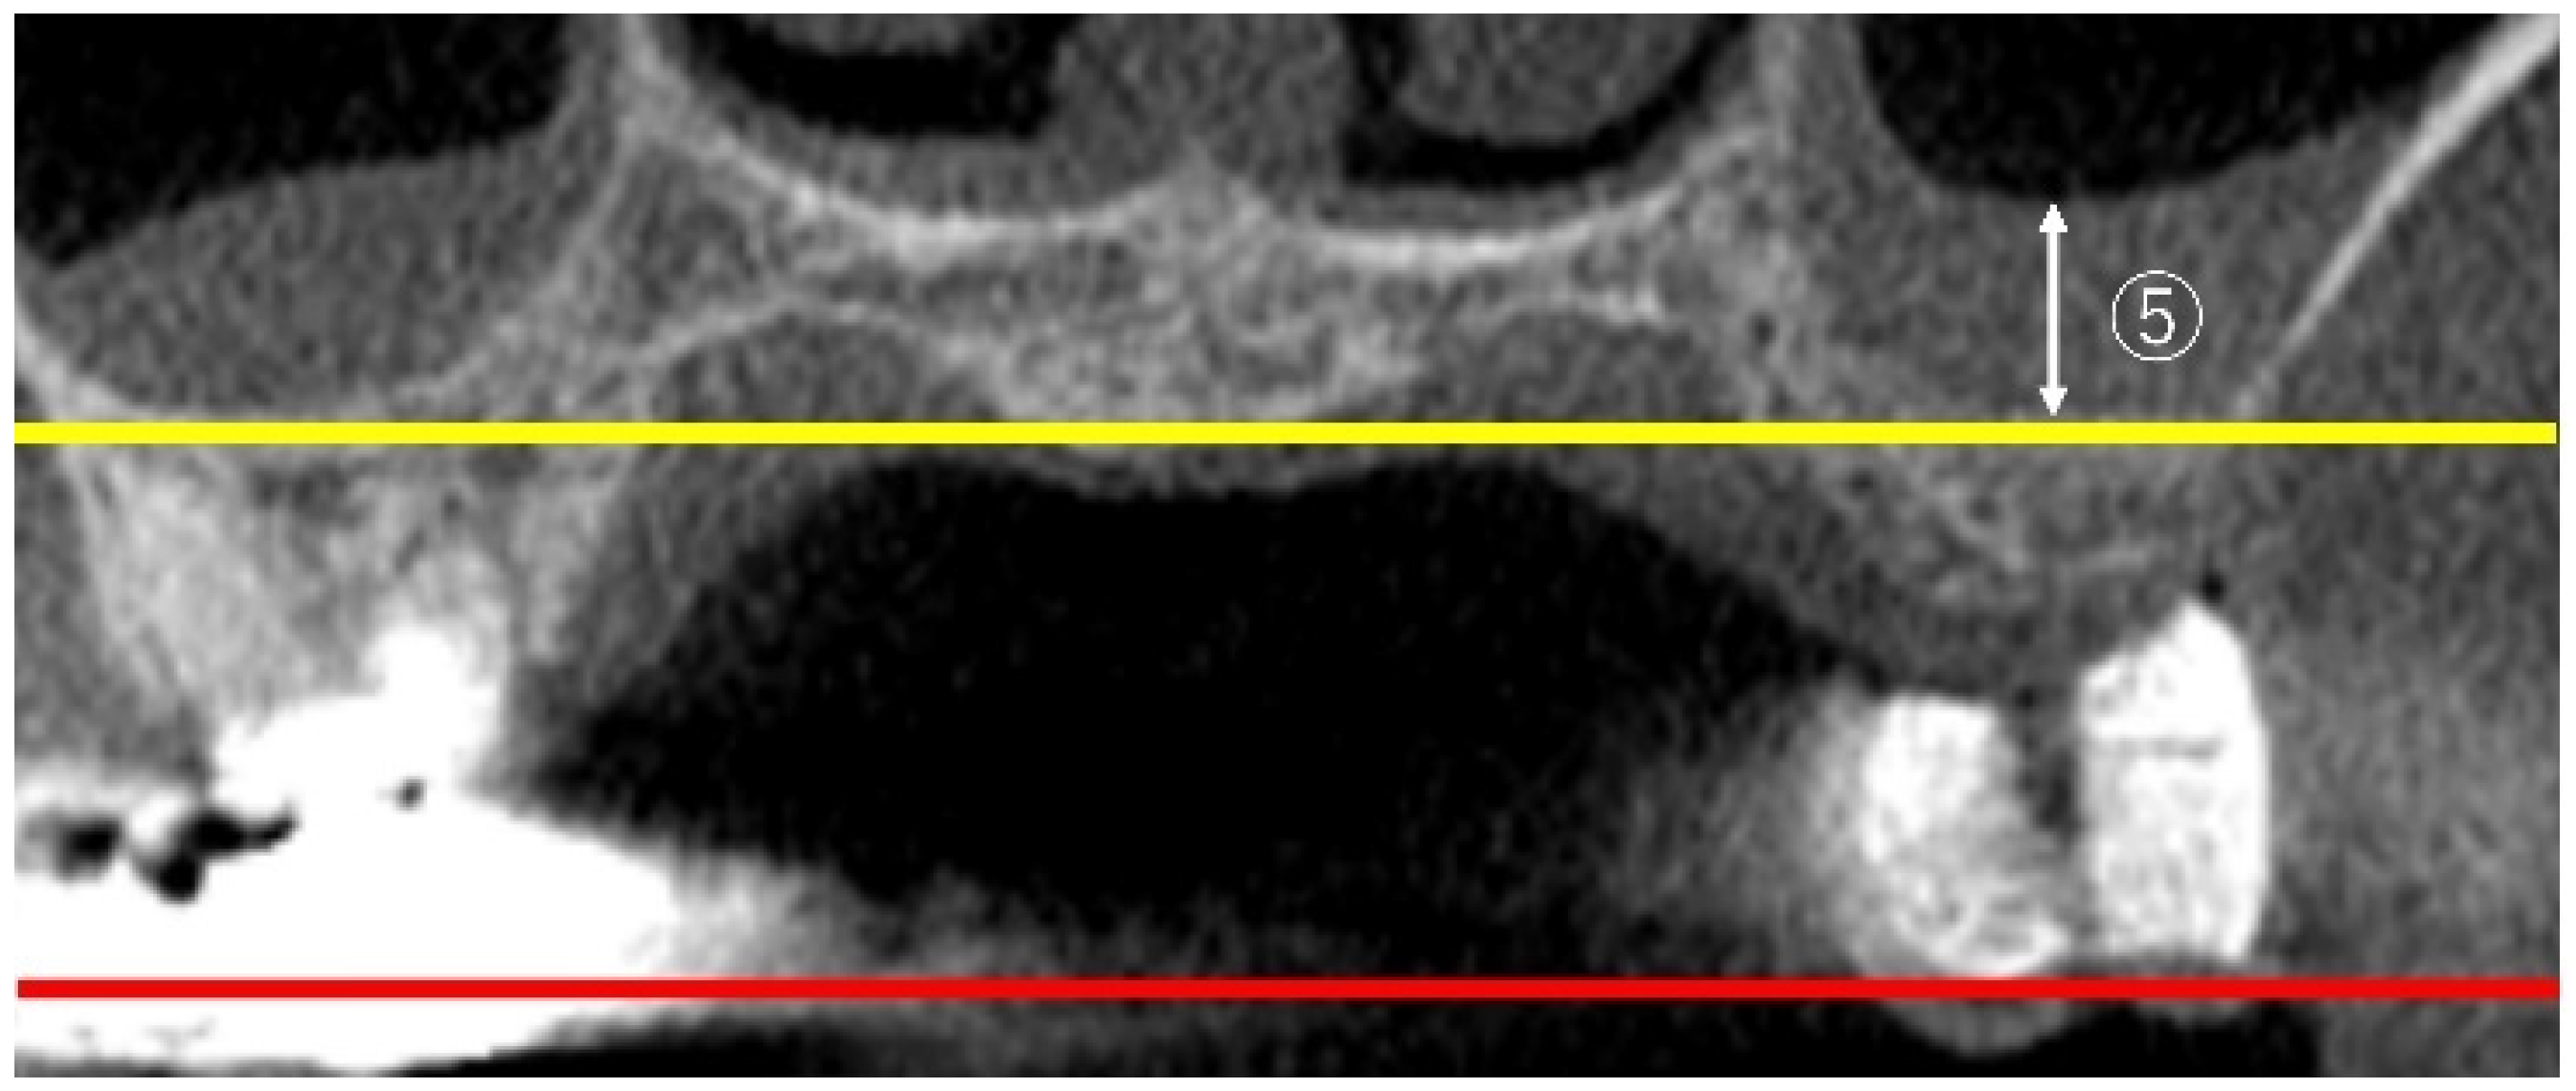

2.2. Measurement Method Using CBCT Images

2.3. Measurement Items

2.3.3. Measurement of Sinus Membrane Thickness (SMT)

2.3.4. Linear Measurements of Maxillary Sinus Length